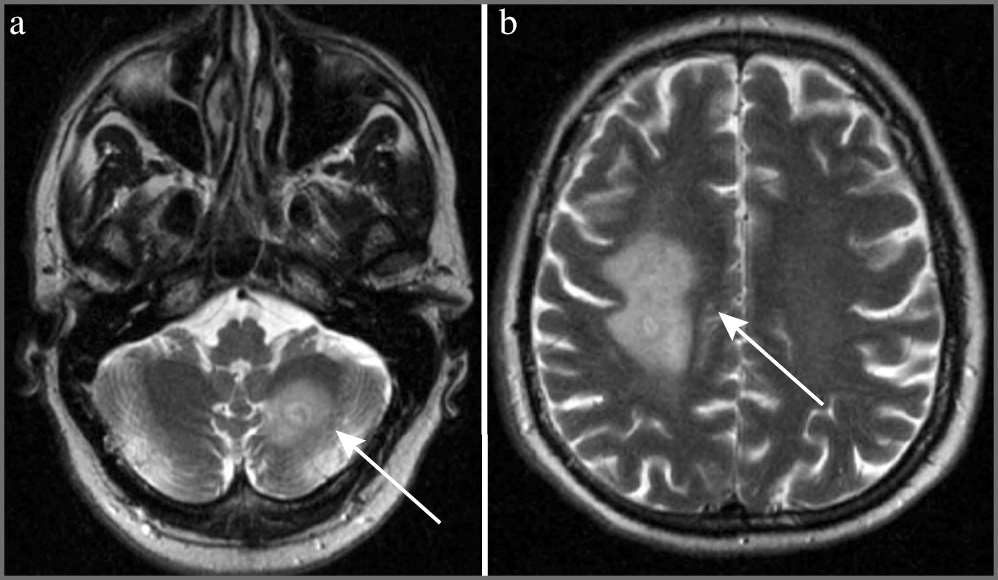

Пациент А. 52 лет поступил в Клинику нервных болезней (КНБ) Сеченовского Университета 03.03.2021 с жалобами на эпизоды системного головокружения, неустойчивость при ходьбе, снижение зрения и слуха на левое ухо. Считает себя больным с 12 ноября 2020 г., когда после переохлаждения отметил повышение температуры тела до 39–40ºС, сухой кашель, снижение слуха на левое ухо. Через 10 дней после самостоятельного лечения дома в связи с сохраняющейся гипертермией пациент госпитализирован в стационар, где подтвержден диагноз коронавирусной инфекции. После выписки из стационара 30.11.2020 пациент самостоятельно прекратил прием всех рекомендованных препаратов, включающих дексаметазон, и через 3 дня возникло ухудшение состояния в виде возбужденности, неадекватного поведения, нарушения сна и развития генерализованного судорожного приступа. Пациент повторно госпитализирован с подозрением на инсульт. По данным проведенной компьютерной томографии (КТ) ГМ от 08.12.2020 патологических изменений не выявлено. Через 4 дня после выписки из стационара пациент отметил слабость в ногах, эпизод системного головокружения, выраженную неустойчивость при стоянии и ходьбе, а также снижение зрения. Указанная симптоматика в течение 1 мес постепенно нарастала, после чего самостоятельно начала регрессировать. МРТ ГМ (без контрастирования) от 28.01.2021: признаки патологических изменений слева в полушарии мозжечка, в перивентрикулярной области правого полушария ГМ и семиовальных центрах с явлениями отека, слева у переднего рога (рис. 1).

Рис. 1. МРТ головного мозга в Т2-взвешенном изображении пациента А. от 18.01.2021.

Очаговые изменения в левом полушарии мозжечка (см. рис. 1, а) и правой перивентрикулярной области (см. рис. 1, b). Анамнез жизни: работник культуры, женат, детей нет. Хронические и перенесенные заболевания: детские инфекции. Вредных привычек нет. Наследственный анамнез по неврологическим заболеваниям не отягощен. В соматическом статусе изменений не выявлено, артериальное давление – 120/80 мм рт. ст., пульс удовлетворительного наполнения, 68 в минуту. Дизурии нет, стул в норме.